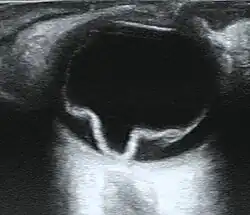

Cross section of retinal detachment | |

If the view of the retina is not clear, imaging techniques such as ultrawide-field fundus photography, B-scan ultrasonography, and optical coherence tomography (OCT) may help to identify a detachment.[8][13][14] Fundus photography provides a detailed view of the back of the eye, potentially revealing retinal tears or breaks.[8][16] On B-scan ultrasonography, a detached retina typically appears as a membrane floating in the vitreous cavity, moving in a wave-like motion.[19] OCT can detect fluid behind the retina, involvement of the macula (the central part of the retina), and other abnormalities within the retinal layers.[8][20]